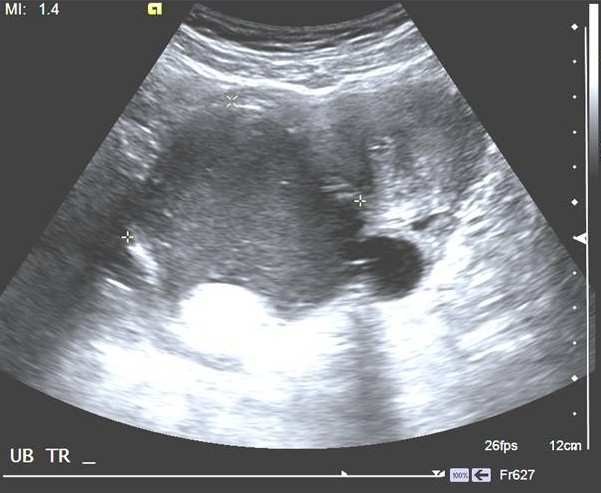

37歲孕婦,G1P0,妊娠36週,血壓180/110 mmHg,接受下列超音波檢查,如圖所示。則該檢查是:

詳解

【107-2 醫學(六) 第54題】承上題,正確的判讀為下列何者?

破題關鍵

媽媽血壓這麼高,胎盤功能通常會受影響,如果臍動脈血流波形異常,就代表胎兒可能缺氧,處於窘迫狀態。